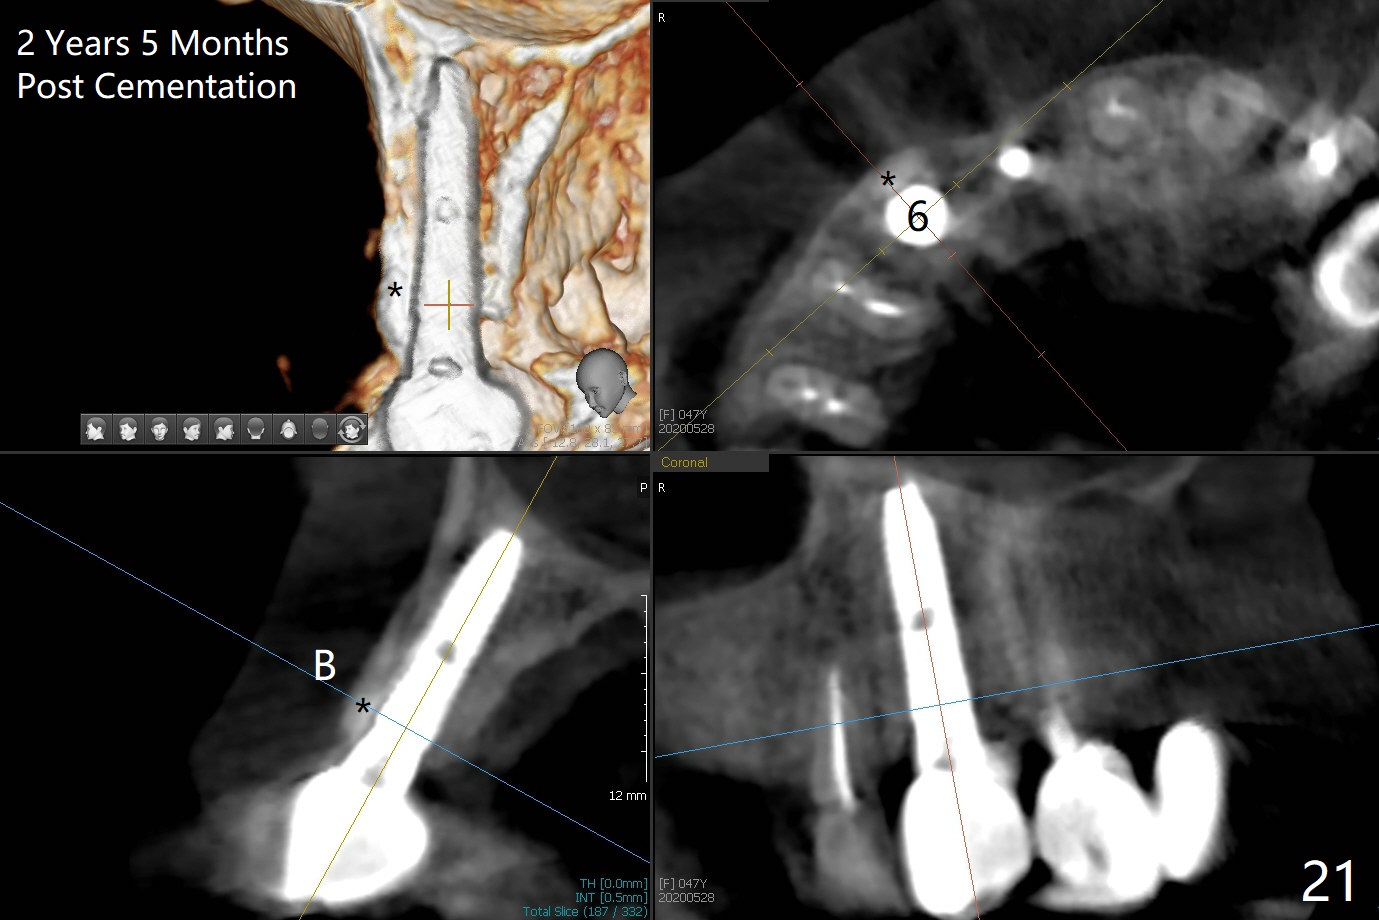

Since the ridge at #7 is ~ 4 mm, a 2.5x14 mm 1-piece implant is placed (Fig.8) after 1.2 mm (Fig.7), and 1.5 mm drills at 12 mm and 2 mm drill at 8 mm. Later the implant is placed deeper (Fig.10). There is no bone loss 7 or 12 months postop, respectively (Fig.11,12). After Diode gingivectomy, there is papillary formation (Fig.13). No provisional is provided after impression (with the abutment torqued at #6) for oral hygiene. With access holes at #6 and 7, crowns are bonded with minimal residual cement (Fig.14 <, which is removed later). There is no hard (Fig.15,16) or soft (Fig.17 *) atrophy 26 months postop, i.e., 13 months post cementation, due to the presence of socket shield (Fig.15 <, as compared to Fig.1). In fact the tooth #8 has mobility and fremitus (short root/poor crown/root ratio, Fig.16); occlusal adjustment is done 13 months post cementation. The crown is dislodged 2 years 1 month post cementation; a prefabricated post is being tried in (Fig.18). There is no atrophy, bone loss or infection at #6 (with socket sheath (*)) or 7 two years 5 months post cementation (Fig.20-27).